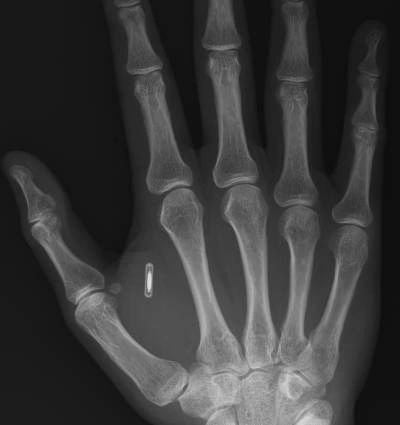

At the present time, computer-assisted biometric identification systems are being developed rapidly and have been readily accepted into our society. Miniature computer chips, using RFID (Radio Frequency Identification) technology, have already been embedded within electronic appliances, retail goods, livestock, and human beings. This is not tomorrow’s science fiction – it is happening today.

In many parts of the world, Applied Digital Corporation’s human implanted RFID microchip (VeriChip) is used to help diagnose Alzheimer’s disease, mental illness, Diabetes, heart problems and it also helps to prevent kidnappings. In the near future, this type of biochip will be widely accepted and implanted for personal identification, protection, monitoring, tracking, commerce, and other uses not yet imagined.

Unfortunately, such biochips store personal identification and the information generated from its use will be stored and maintained in a computer database. Your body becomes a tagged asset that is monitored and whose behavior will be tracked. Implanting the microchip in the body alters a person’s physically, mentally and ultimately – spiritually. The problem that arises from the use of biochip in humans is more than an aesthetic, medical, political, or legal issue.